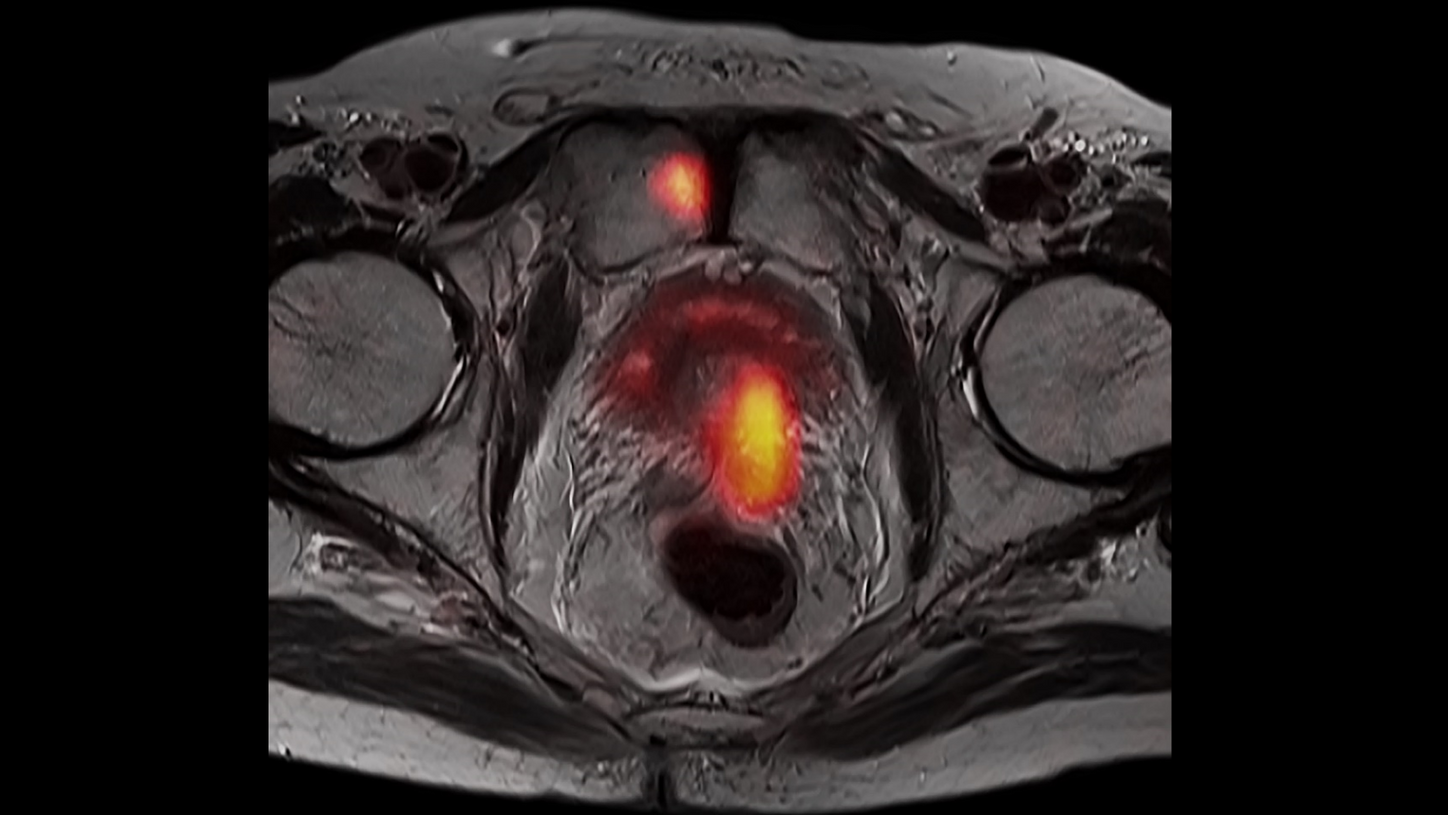

BIOGRAPH One is designed to support one patient-centric pathway to personalized care. By seamlessly integrating PET and MR into one comprehensive exam, it will support clinicians from diagnosis and staging, through a personalized therapy decision to regular therapy assessments to excel precision and support one streamlined approach.

BIOGRAPH One is designed to excel in PET/MR precision to support confident diagnostic decisions. Featuring the Optiso UDR Pro detector with the largest 35 cm axial FOV2 in PET/MR, it is designed to enable comprehensive capture with excellent sensitivity and ultra-fast TOF3 in real time – delivering clear, detailed images.